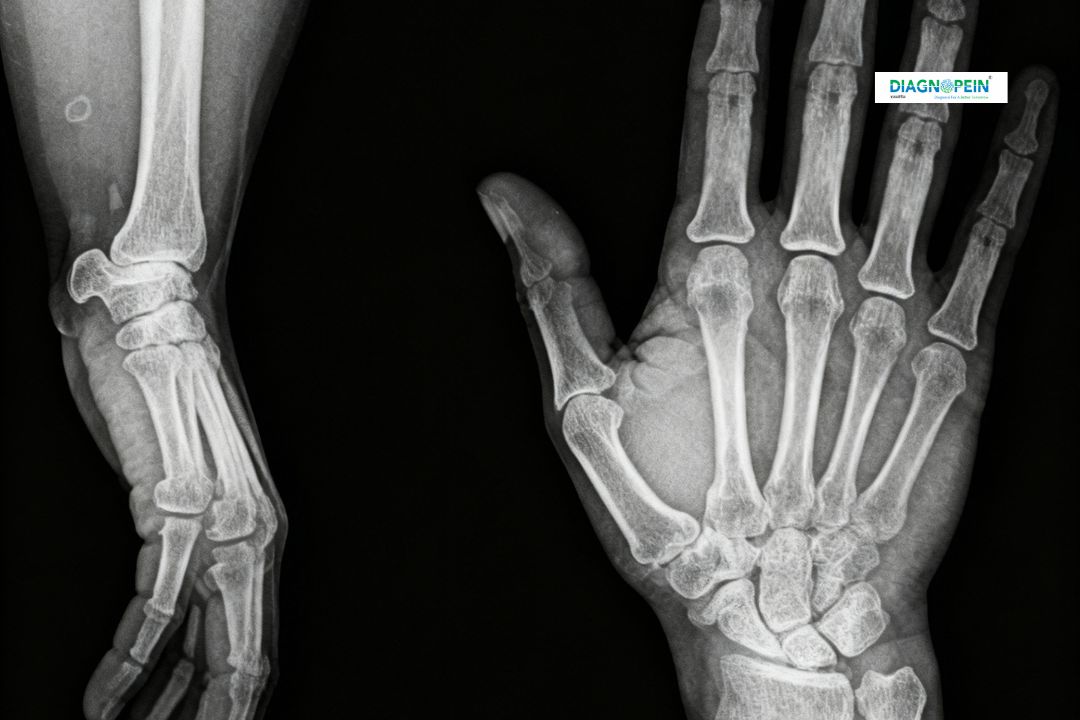

An X-Ray Right Palm AP/LAT (Anteroposterior and Lateral view) is a specialized diagnostic imaging test that captures detailed images of the bones, joints, and soft tissues of the right hand. It helps doctors identify fractures, dislocations, degenerative bone conditions, and infections affecting the palm and wrist region. At Diagnopein in karad, high-quality digital X-ray machines ensure precise images with minimal radiation exposure, helping clinicians make accurate diagnoses efficiently.

The AP (anteroposterior) view shows bones from front to back, while the LAT (lateral) view displays them from the side. Together, these two angles provide a comprehensive understanding of the bone structure, making it easier for orthopedists to assess injuries and joint alignment in detail.